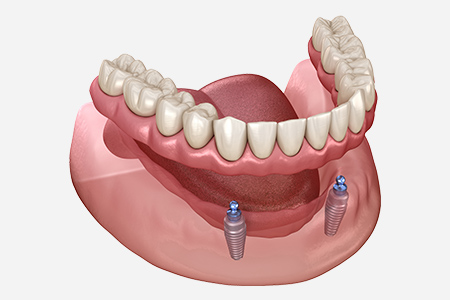

インプラントを活用した入れ歯治療

「入れ歯が安定せず噛みにくい」「外れやすい」といったお悩みを抱えるかたに向けて、当院ではインプラントオーバーデンチャーをご提案しています。顎の骨に埋め込んだインプラントを支えにして、入れ歯を安定させる治療法で、見た目や噛む力の回復に加え、取り外し式のためお手入れもしやすいのが特徴です。総入れ歯が合わないかたや、しっかり噛める入れ歯を希望されるかたに適しています。